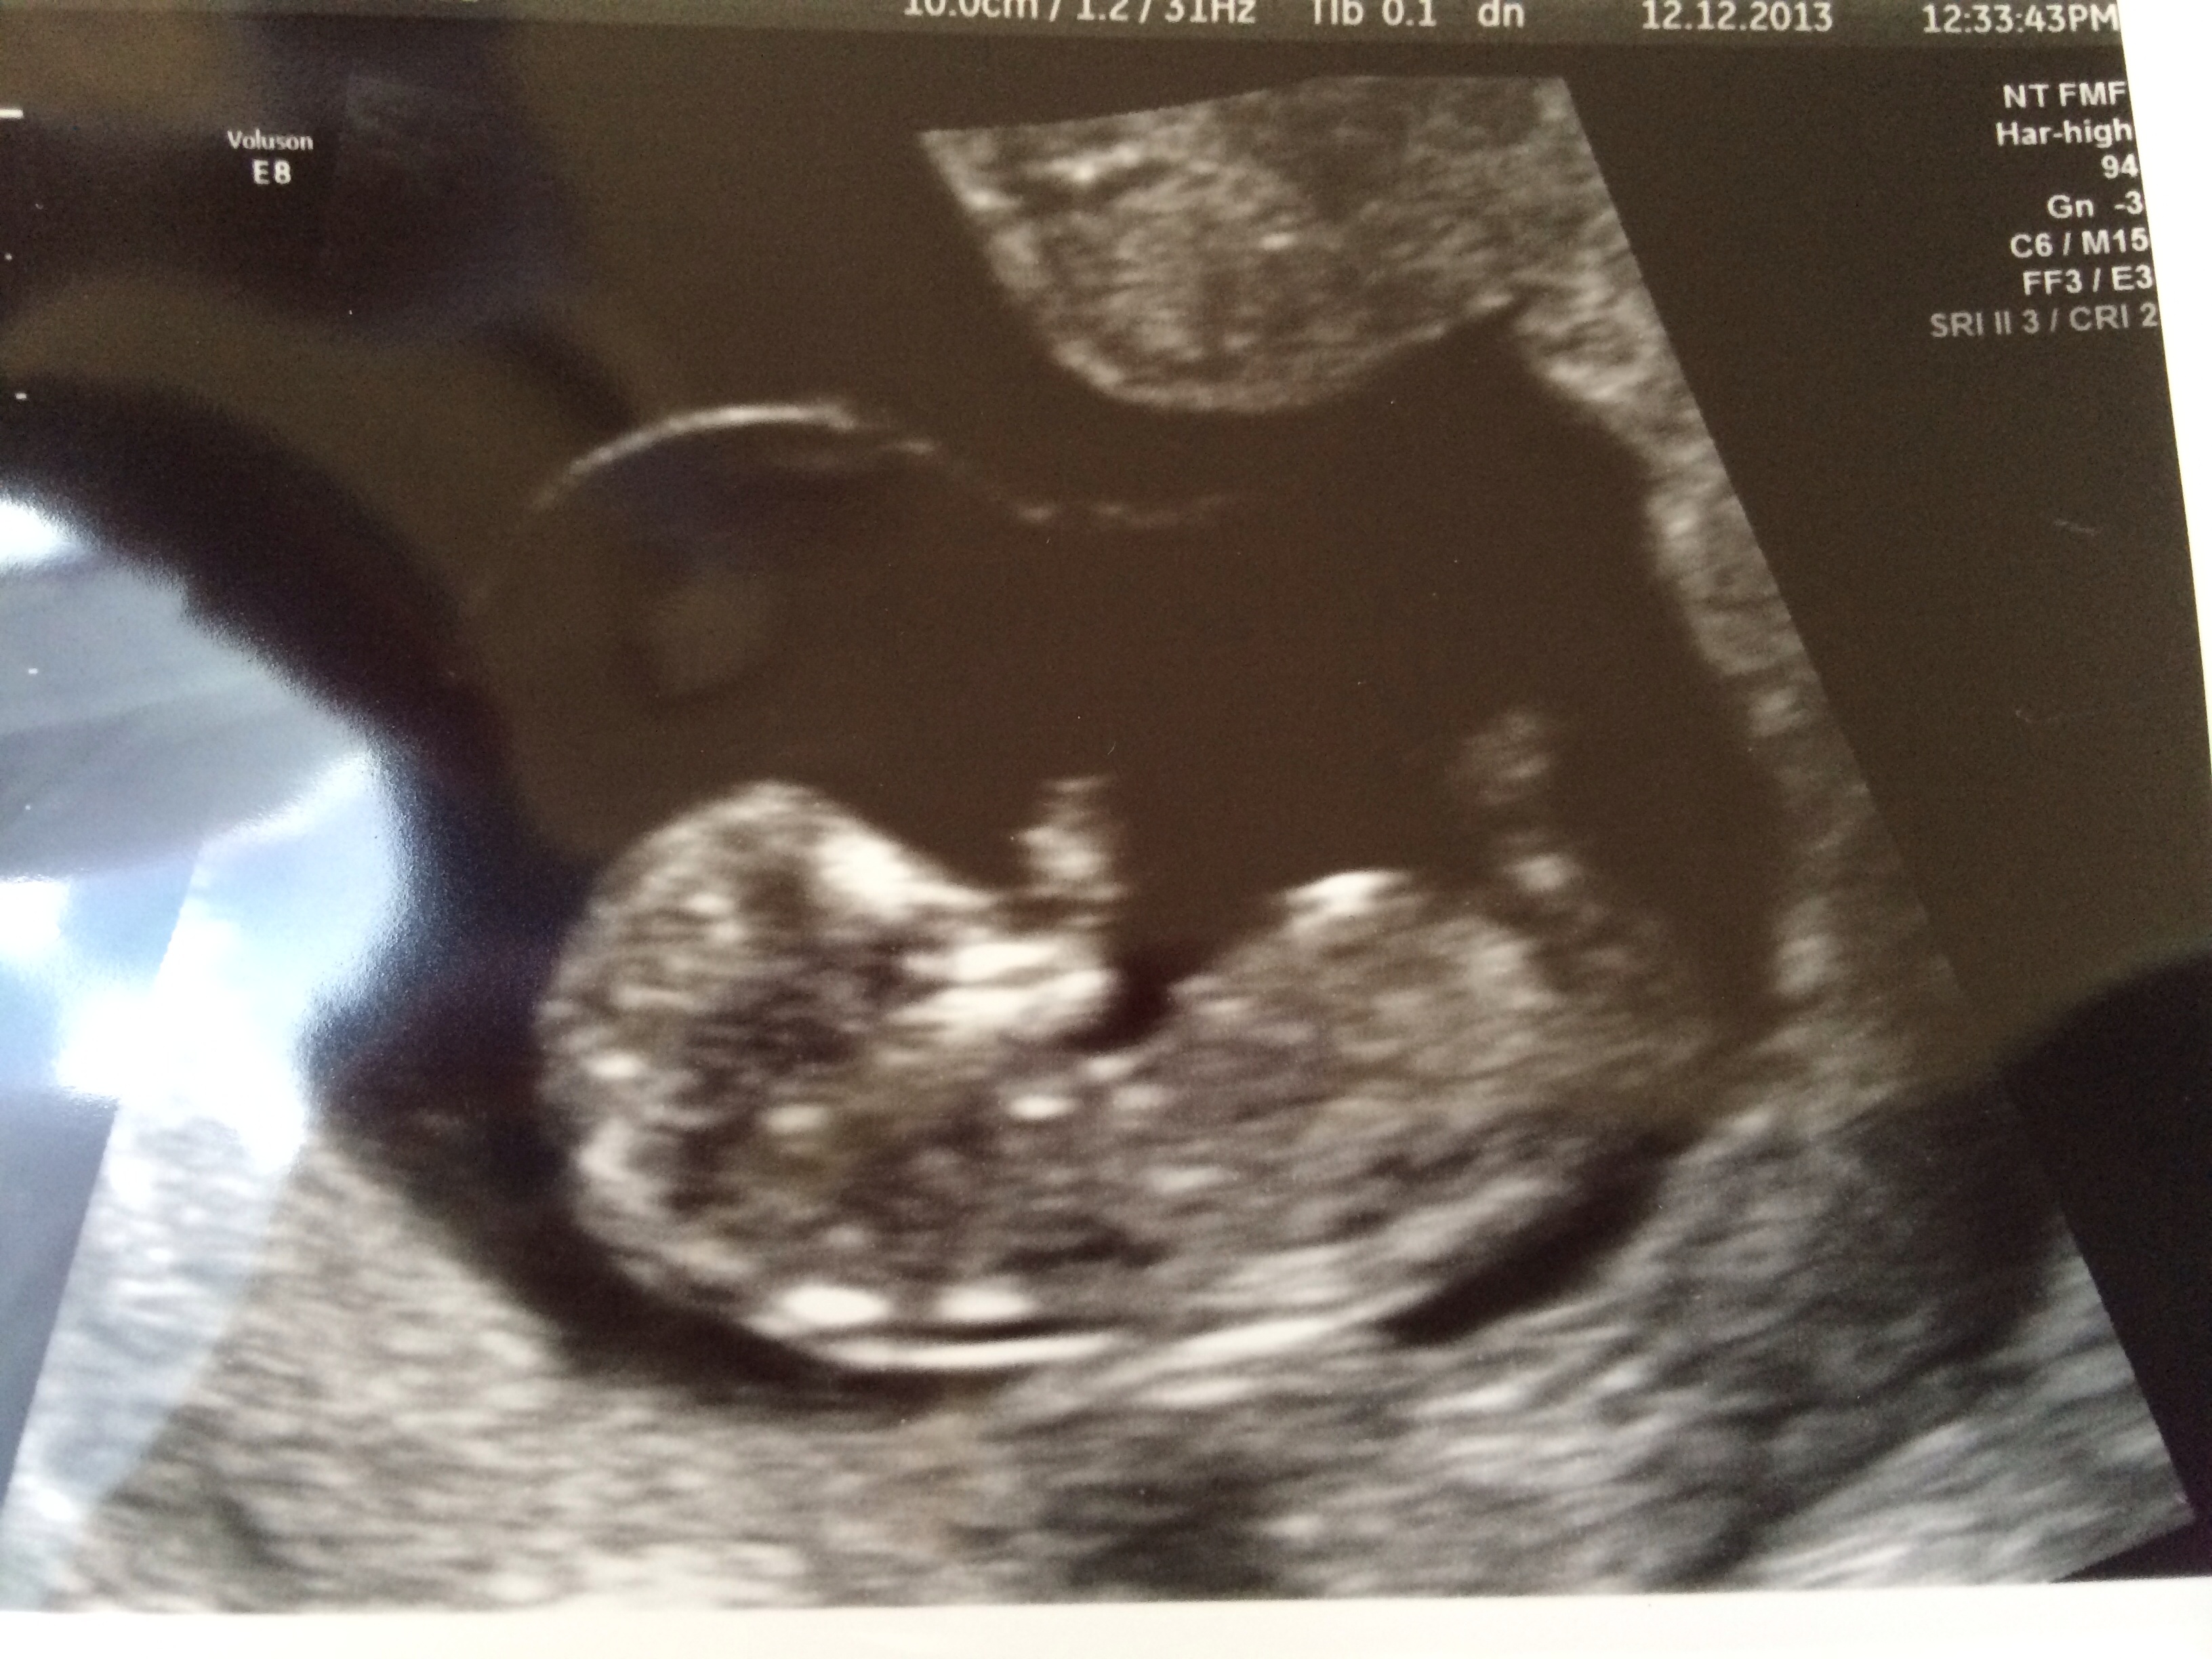

I had an ultrasound yesterday and wondered if there were any skull theory guesses, only 11 weeks. Not sure if it's too early, having NT scan next week.